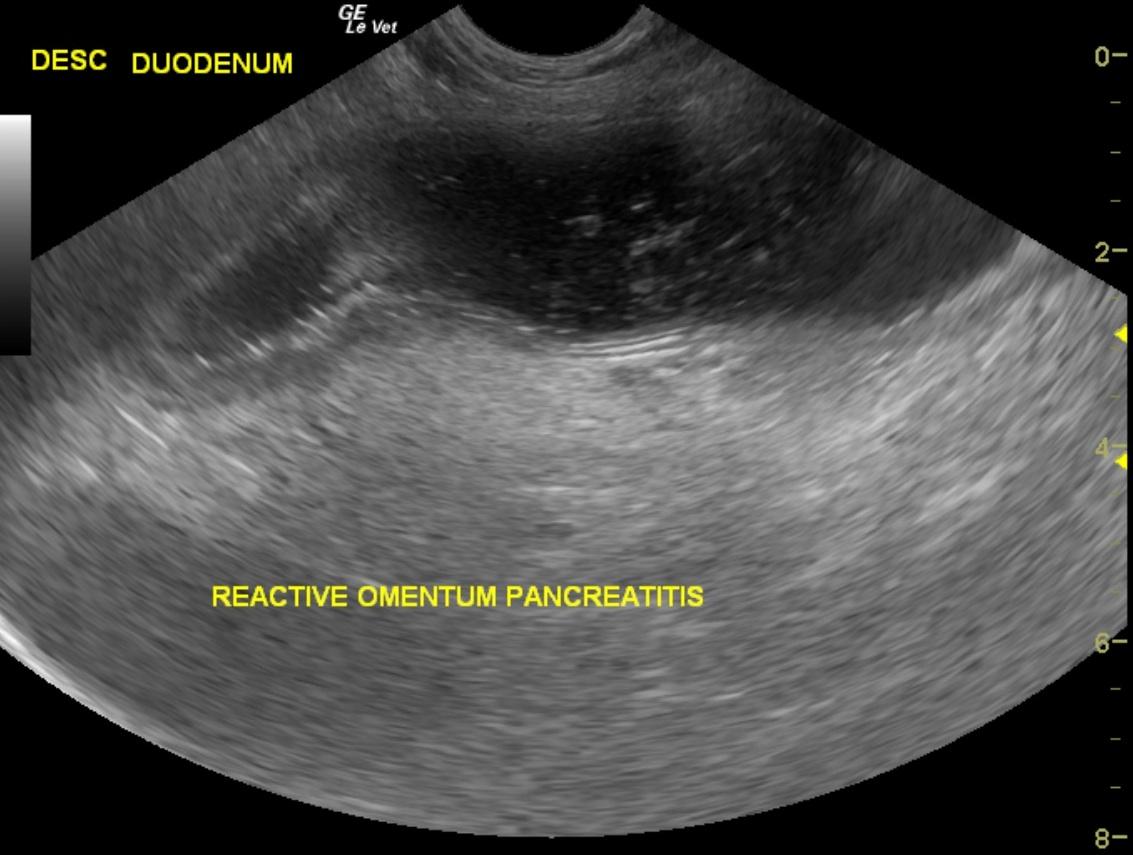

A 7-year-old MN Dachshund was presented for anorexia, dehydration, and vomiting for two days. Recent CBC and chemistry panel had shown elevated HCT, neutrophilia, monocytosis, low sodium, low potassium and low chloride, and elevated ALP; elevated AST activity, elevated amylase, increased anion gap, increased bicarbonate, elevated urea, elevated cholesterol, elevated creatinine, elevated phosphate and elevated CK. 4DX snap ELISA was negative and urinalysis and fecal examination within normal limits.